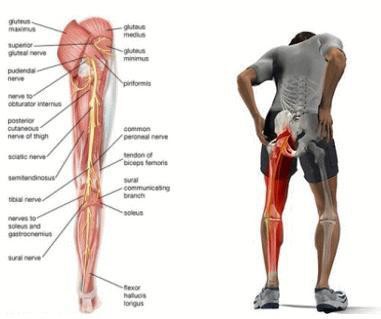

坐骨神経とは腰から足に向かって伸びる体の中でもっとも大きな神経です。この坐骨神経がなんらかの圧迫や刺激が加わることで現れる、痛みや痺れなどの症状を言います。

多くの方は、腰の痛みから始まりお尻や太もも、すね、足先などに違和感から痛み、痺れが現れてきます。

しかし坐骨神経は腰から足の先まで繋がっているため、圧迫や刺激をする場所が腰だけに限らず股関節や膝関節、足首に原因があることも考えられます。

坐骨神経がお尻や太ももの筋肉のコリや血行障害を痛みという信号で脳に送っていて、神経そのものが痛い訳ではありません。

そのため、臀部痛(お尻の痛み)や大腿後部痛(太ももの裏側の痛み)、下腿部痛(ふくらはぎやスネの痛み)に対して痛み止めや湿布が処方され、これに効果がなければブロック注射や手術が勧められます。